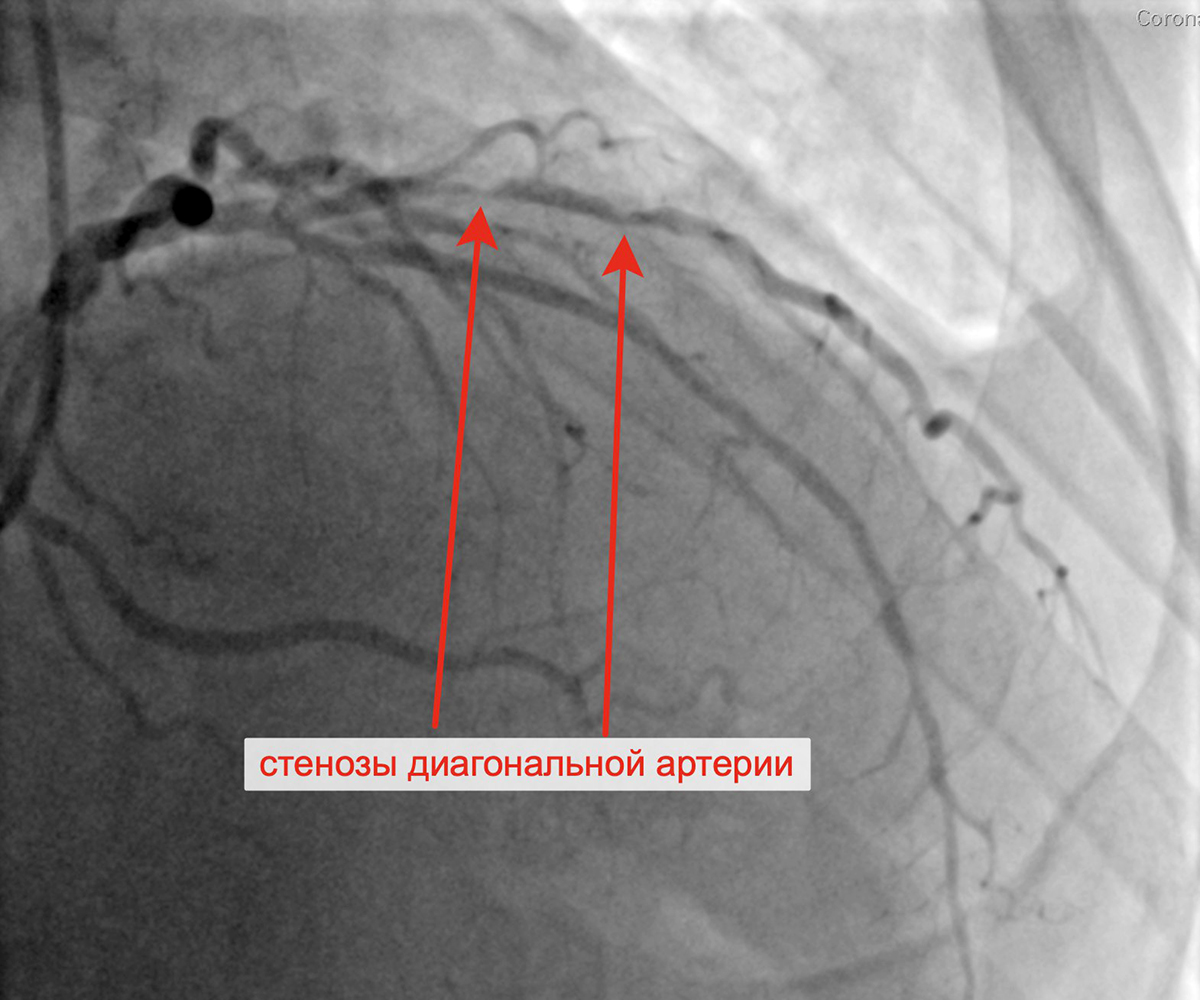

Передняя межжелудочковая артерия (ПМЖА): ПМЖА без ангиографически значимого стенозирования, стеноз проксимального и среднего сегмента крупной ДА 80% и 85% соответственно.

Вторым этапом в январе 2023 г. принято решение о проведении пациенту с персистирующей формой ФП, ГКМП, сохраняющейся клиникой стенокардии напряжения, известной коронарной анатомией, многососудистым поражением коронарного русла баллонной ангиопластики и стентирования крупной диагональной артерии (ДА) (1 стент с лекарственным покрытием). При контрольной ангиографии: стент и ДА проходимы, позиционирование стента адекватное, диссекции или остаточного стеноза в стентированном сегменте ДА нет, кровоток TIMI 3 по ДА и всем ее ветвям.

Стенозы диагональной артерии Выполнена баллонная ангиопластика ДА

Выполнено позиционирование и имплантация стента в ДА Финальный результат стентирования ДА